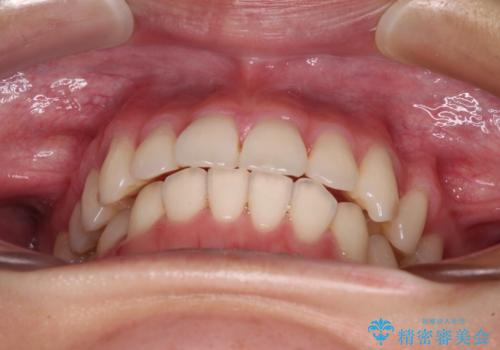

- 咬み合わせが悪いとのことで来院された患者様です。

ぱっと見はインビザラインによる矯正治療も可能と思われましたが、歯根が最も長い犬歯がクロスバイトになっており、インビザラインでは対応困難と判断され、ワイヤー装置にて矯正治療を行うこととしました。

クロスバイトになっている犬歯は、歯の移動に伴い装置を張り替えていくことで対応することとしました。

クロスバイト改善中には歯髄壊死を起こすリスクがあるため、神経に問題がないか確認しながら治療を進めて行く必要があります。

思っていたよりも早くクロスバイトは改善され、歯髄壊死に至ることなく、無事に治療を終えることができました。